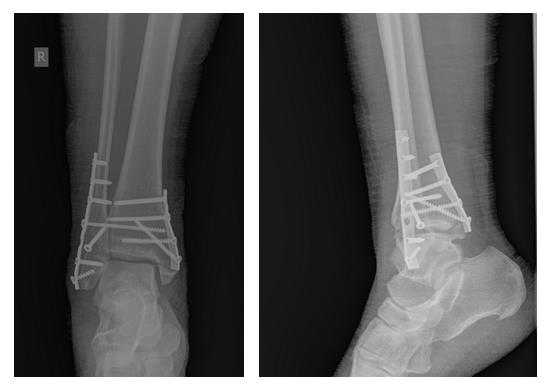

Пациентка Л. 50 лет, травма в быту, получила закрытый перелом обеих лодыжек с вывихом стопы кнаружи и кзади. Данный случай интересен значительным повреждением мягких тканей произошедшем при травме и потребовавшем значительных усилий в борьбе с отёком, а также морфологией перелома внутренней лодыжки, сломавшейся одним большим блоком вместе с задним краев большеберцовой кости, что потребовало её фиксации при помощи пластины и винтов.

В связи с выраженным отёком мягких тканей, высоким риском некроза краёв ран и инфекционных осложнений пациентке с целью предоперационной подготовки выполнялись скелетное вытяжение, сосудистая и метаболическая терапия, лимфодренаж, физиотерапия. После спадения отёка, на 3 день после поступления выполнено оперативное вмешательство: открытая репозиция, остеосинтез переломов наружной и внутренней лодыжек пластинами и винтами.

Через 4 дня пациентка выписана на амбулаторное долечивание. Послеоперационные раны зажили первичным натяжением, швы удалены через 14 дней.

Через 6 недель после первичного вмешательства произведено удаление позиционного винта, пациентка приступила к активной разработке движений в голеностопном суставе.

Амплитуда движений через 8 недель после травмы и оперативного вмешательства по поводу этого тяжёлого повреждения близка к полной. Пациентка ходит с полной опорой, не используя костыли или трость, не хромает, боли не беспокоят. Сохраняется умеренный отёк в области голеностопного сустава.